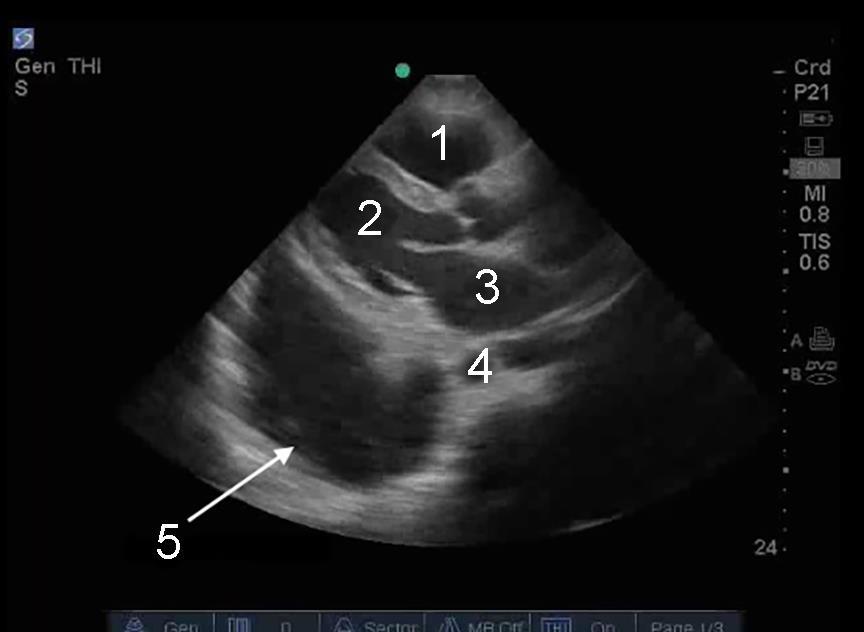

Heart Parasternal Long Axis (PLAX) Large Pleural Fluid Image

1. Right Ventricle (RV)

2. Left Ventricle (LV)

3. Left Atrium (LA)

4. Aorta

5. Large Pleural Fluid (Effusion)